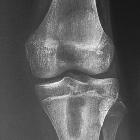

Plain radiograph

- lytic lesion often in an oval configuration that is oriented along the long axis of the bone

- surrounded by a thick dense rim of reactive sclerosis that fades imperceptibly into surrounding bone

- lucent tortuous channel extending toward growth plate prior to physeal closure (pathognomonic)

- periosteal new-bone formation +/- adjacent soft-tissue swelling

- may persist for many months